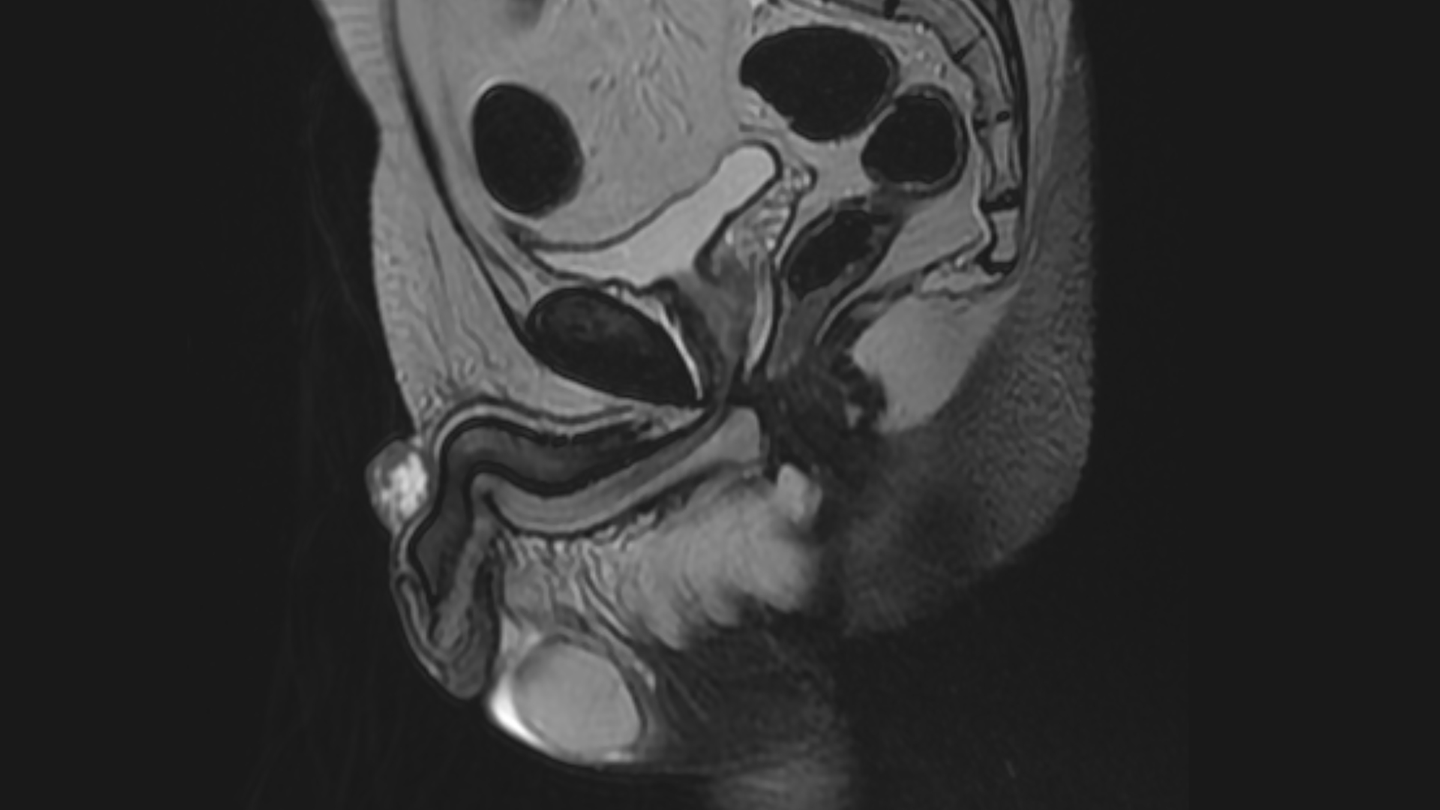

Röntgenaufnahme eines Penis mit Peniskrebs

Peniskrebs - Späterkennung wegen Schamgefühlen

Peniskrebs ist mit rund 800 Neuerkrankungen pro Jahr in Deutschland eine seltene Erkrankung, die Betroffenen sind meist um die 70 Jahre alt. Typische Symptome: Hautveränderungen, Verhärtungen oder Schwellungen an Eichel oder Vorhaut, Ausfluss, Jucken oder Blutungen aus dem Penis sind typische Symptome. Früh entdeckt sind die Aussichten auf Heilung gut. Leider wird Peniskrebs oft sehr spät erkannt, da Männer aus Schamgefühl meist sehr spät einen Arzt aufsuchen. Einige Formen des Peniskrebses werden durch Infektionen mit Humanen Papillomavirus (HPV) ausgelöst. Dagegen kann man sich Impfen lassen.